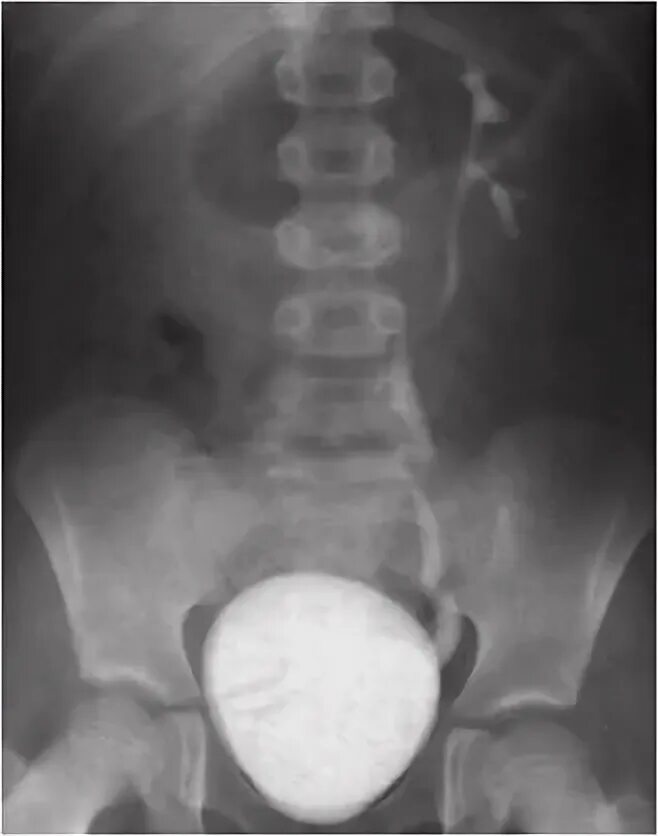

Мегауретер у детей что это